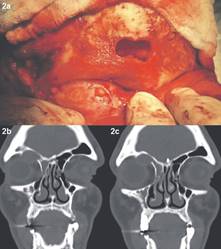

Se realizó una punción aspirativa para drenaje y cultivo bacteriano. Posteriormente se realizó la exodoncia segundo molar superior derecho (diente 1.7) que clínicamente presentaba gran destrucción coronaria y dolor a la percusión vertical. Tras la exodoncia, se observó una comunicación bucosinusal con secreción profusa de contenido purulento desde el seno maxilar. Una semana después del ingreso se realizó el drenaje abierto del seno frontal a través de un colgajo coronal (Fig. 2a), por parte del equipo Otorrinolaringología y Neurocirugía, donde se descartó compromiso de la tabla posterior del seno frontal, y adicionalmente se realizó la desfuncionalización del seno frontal por vía endoscópica nasal.

El paciente fue dado de alta 5 días después con controles ambulatorios por Otorrinolaringología y Cirugía Maxilofacial. Un mes después de la cirugía presenta cierre espontaneo y completo de comunicación bucosinusal, y ausencia de cicatrices o defectos a nivel frontal.